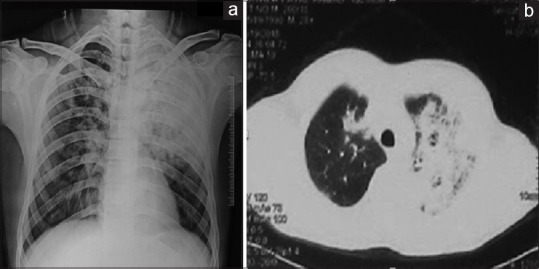

Results: 176 patients (age 20 to 90 years, median 60 years; 109 (61.9%) male) participated. Eighty-nine (50.6%) patients were current smokers. Chest radiographs revealed lobar consolidation as the most common finding (n = 97, 55.1%), followed by pulmonary infiltrates (n = 73, 41.5%) and pleural effusion (n = 6, 3.1%); 44 (25%) patients had multi-lobar consolidation The rates of radiological resolution at 2, 4, 8, and 12 weeks follow-up were 30%, 38.5% (cumulative 68.5%), 25.7% (cumulative 94.2%), and 5.9% (cumulative 100%) of patients, respectively. The average time taken for radiological resolution was 31.49 (±20.2) days in 70 cases, where documented. On multi-variate analysis, smoking was an independent factor for delayed radiological resolution (P = 0.007).